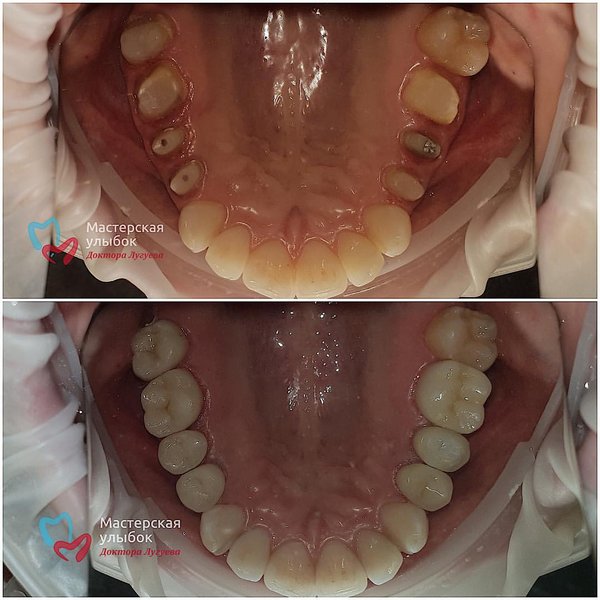

Люблю лечение по сегментам! Сразу все анестезировали, изолировали,вылечили и можно радоваться жизни . Работа врача: Лугуева Арслана. . Запись по тел.: ️ #